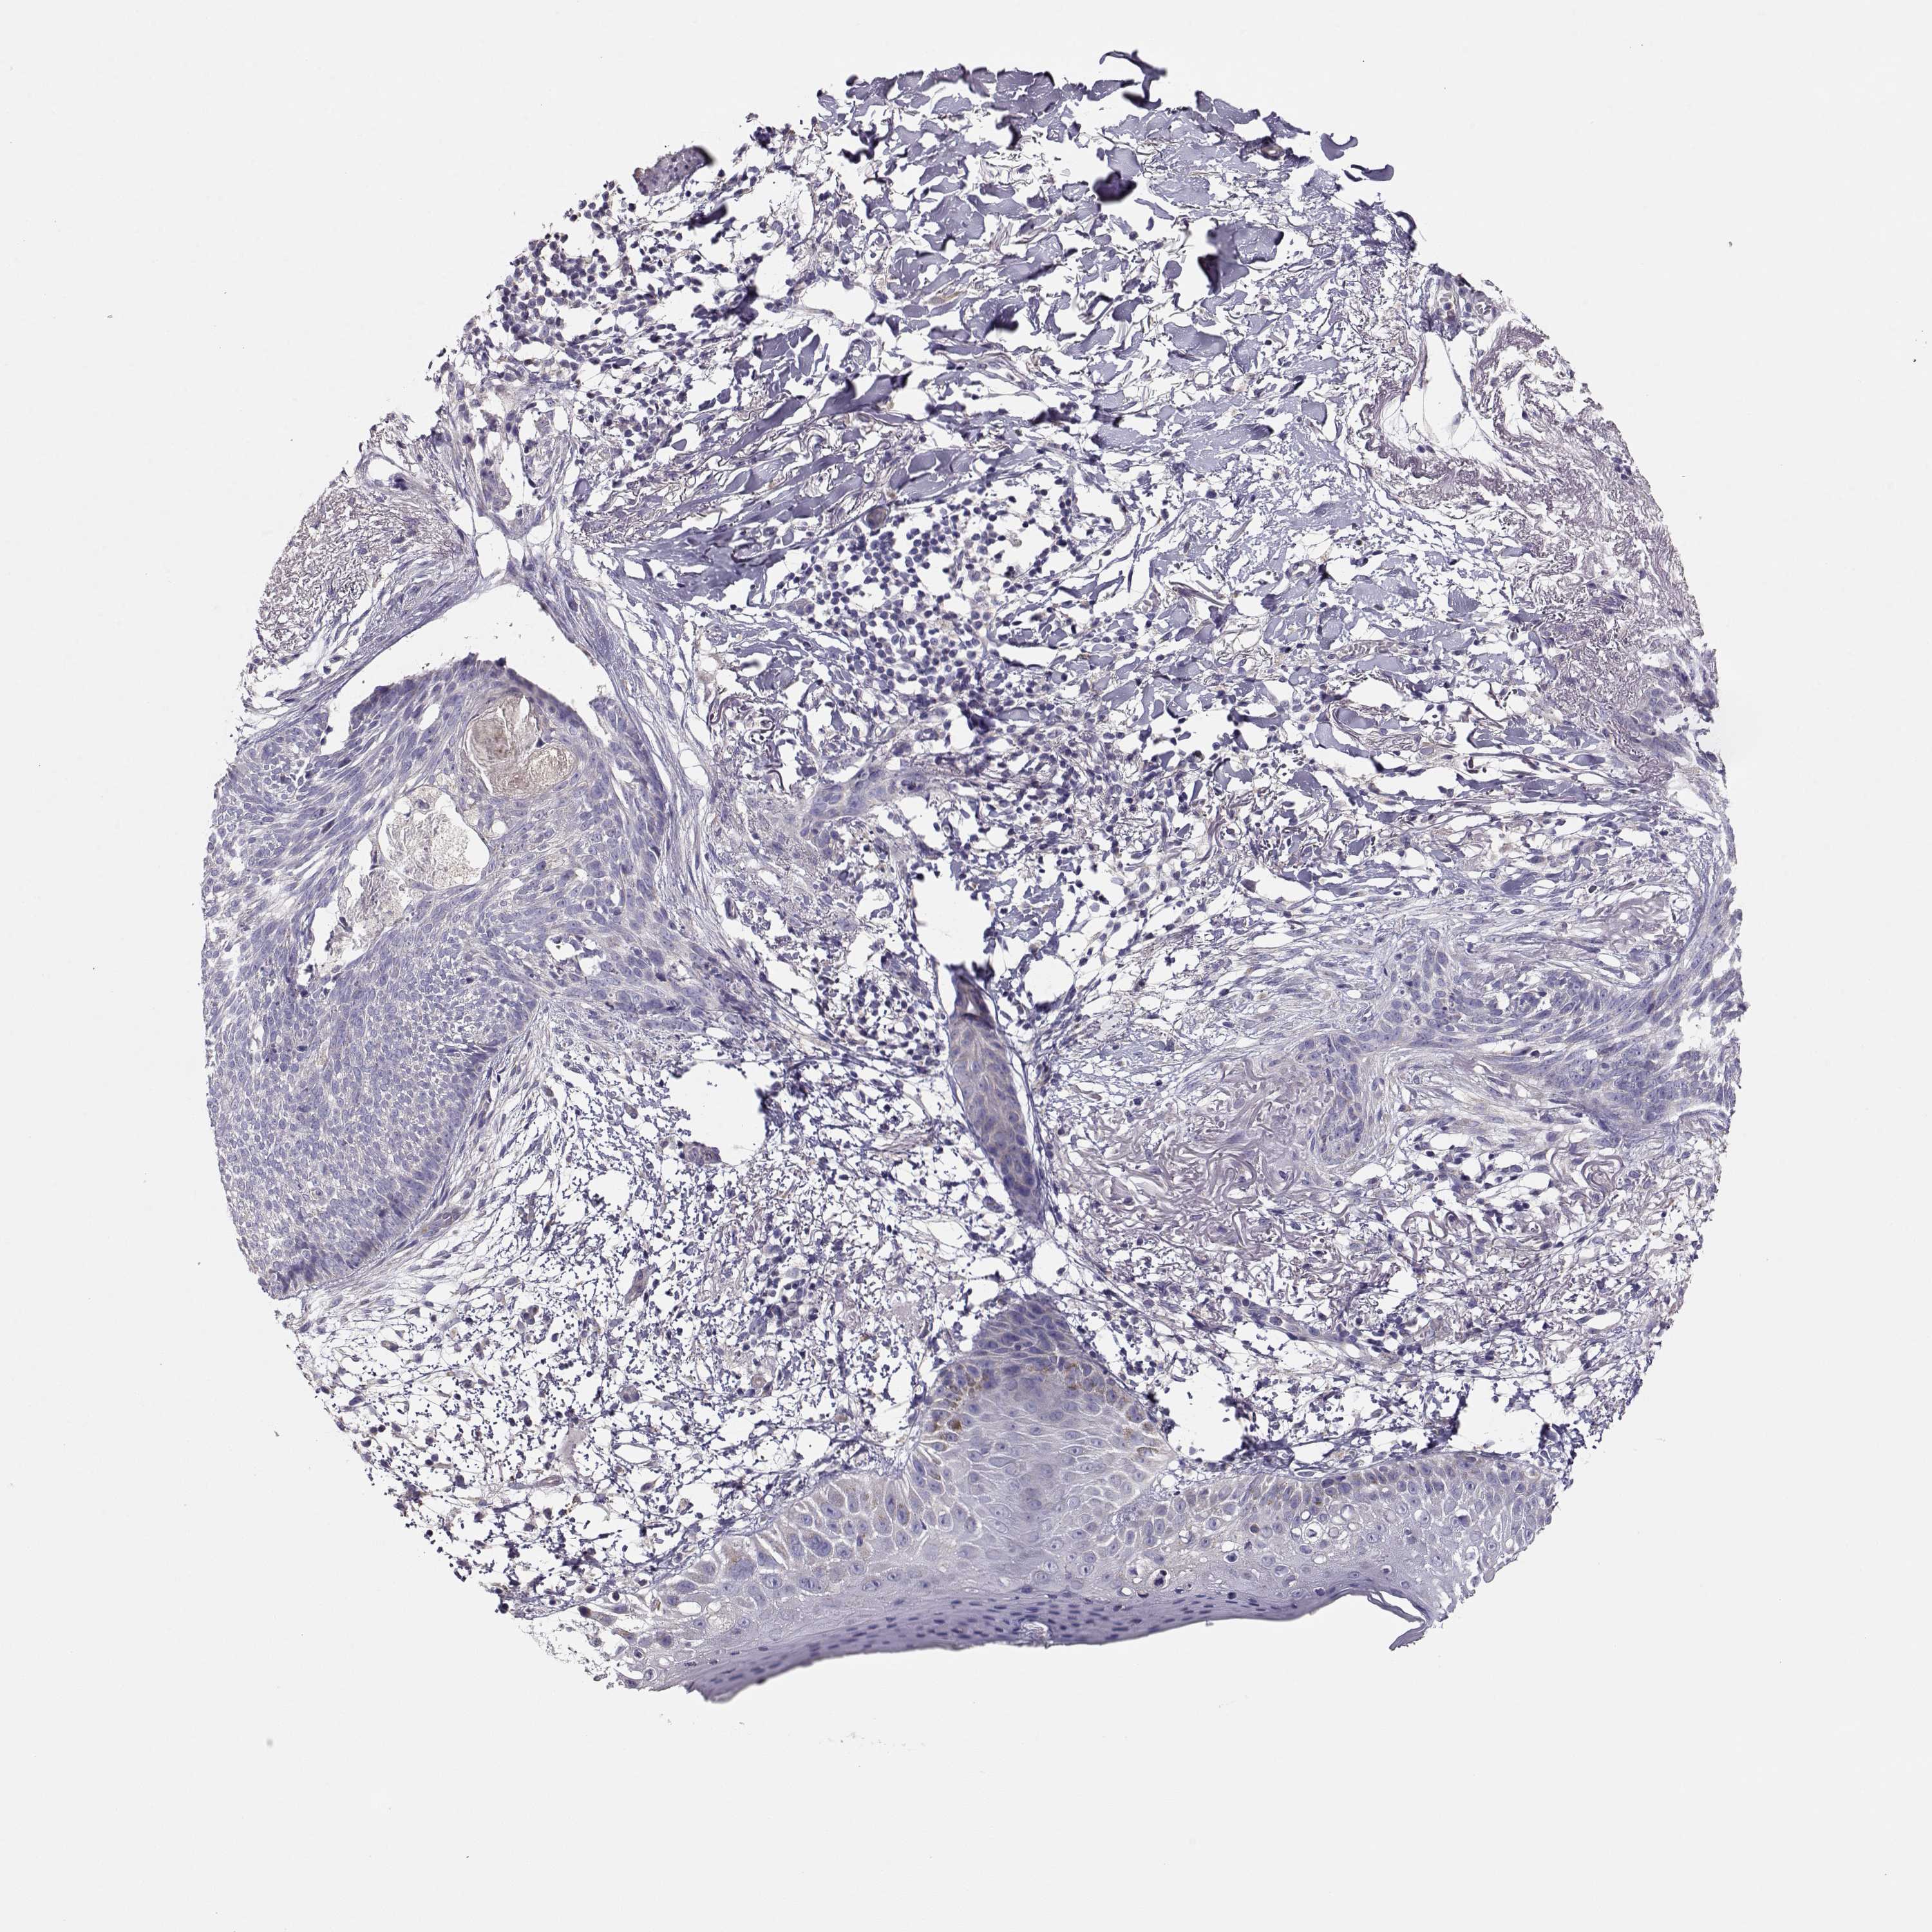

Basal cell and squamous cell cancer

SKIN CANCER - Protein expressioni

A mouse-over function shows sample information and annotation data. Click on an image to view it in a full screen mode. Samples can be filtered based on level of antibody staining by selecting one or several of the following categories: high, medium, low and not detected. The assay and annotation is described here.

Each image is clickable and will lead to virtual microscopy that enables deeper exploration of all samples and also displays staining intensity scores, fraction scores and subcellular localization as well as patient and tissue information for each sample.

Antibody HPA073303

Basal cell carcinoma